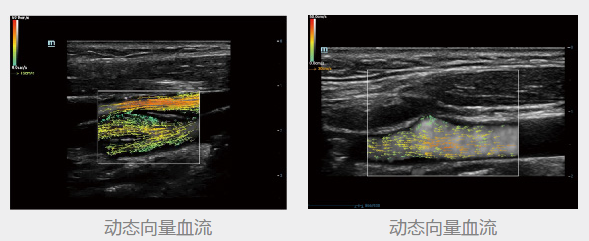

动态向量血流

动态向量血流V-Flow

通过彩色编码的向量箭头来追踪血流速度的大小和方向,生动且准确地显示外周血管的血流动力学特征,包括血管的管径、走行、分布和血管的丰富程度。依靠其高性能的彩色多普勒超声功能,能够显示直径在两毫米以下的细小血管,以及低速血流、低流量的血流,用于评价脏器血流灌注和病灶的血供特点,且无角度依赖,是极具价值的血流动力学研究工具。